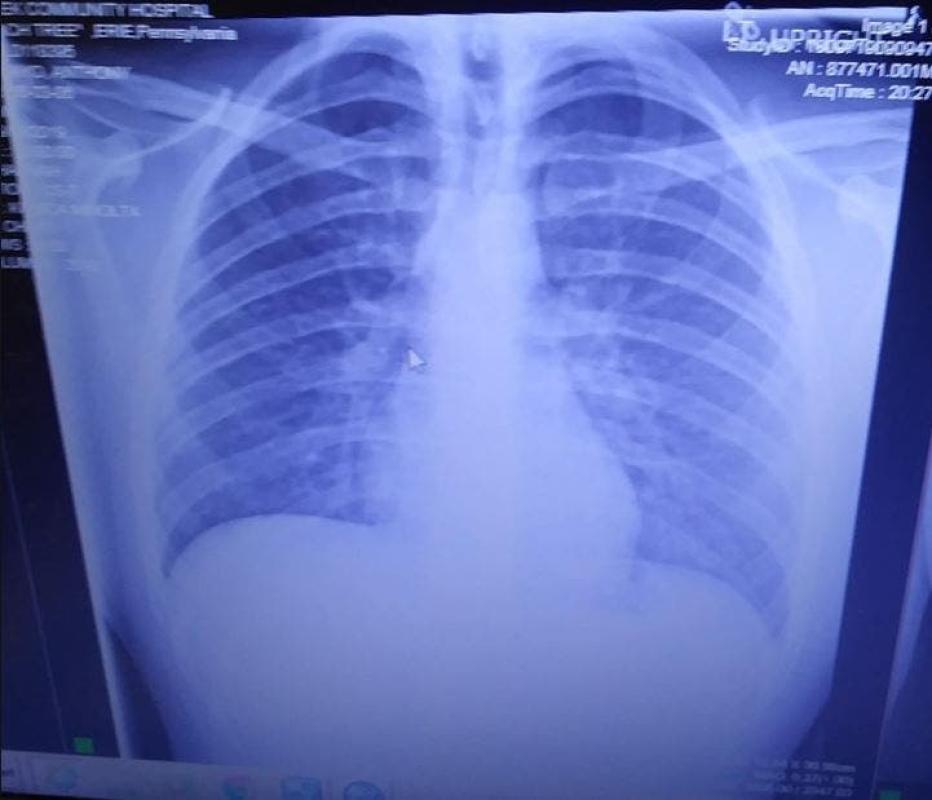

Los pulmones del joven estaban muy congestionados y sus niveles de oxigeno se estaban agotando, Anthony tenía un 36% de nivel de oxigeno en sus pulmones, cualquier cifra debajo del 90% es alarmante.

Por su parte, la madre de Anthony abrió un página para recaudar fondos para la recuperación de su hijo y se refirió a su estado de salud: "El pulmón izquierdo está aproximadamente en un 80% congestionado, mientras que el derecho un 50%'', escribió Tanya Marie, quien además adjuntó las radiografías.